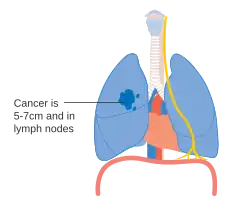

- Diagrams of main features of staging

Stage IIA lung cancer -

Stage IIB lung cancer -